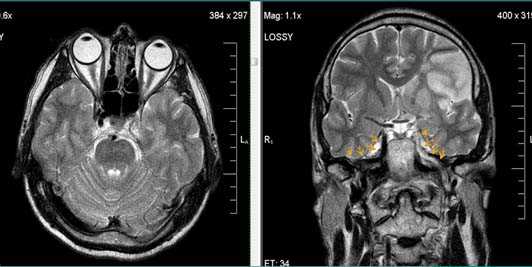

Бассейн кровоснабжения левой верхней мозжечковой артерии, острая стадия НМК.

Зона подострого ишемического НМК, в бассейне правой средней мозговой артерии. В режиме Т1 визуализируется симтом «вуалирования»- изоинтенсивность МР-сигнала.

Подострая стадия ишемического НМК. При внутривенном контрастировании определяется накопления КВ в бороздах на уровне зоны ишемии (гиральный тип усиления).

Валлеровская дегенерация вследствие инсульта в бассейне средней мозговой артерии в левом полушарии большого мозга. Р1_А1К-изображения (а, b) и Т2-ВИ в аксиальной плоскости (с). В зоне, кровоснабжаемой левой средней мозговой артерией, визуализируется кистозный дефект с глиозом (а). Определяется повышенная интенсивность сигнала от пирамидного пути в левой ножке мозга (b) и в продолговатом мозге слева (с).